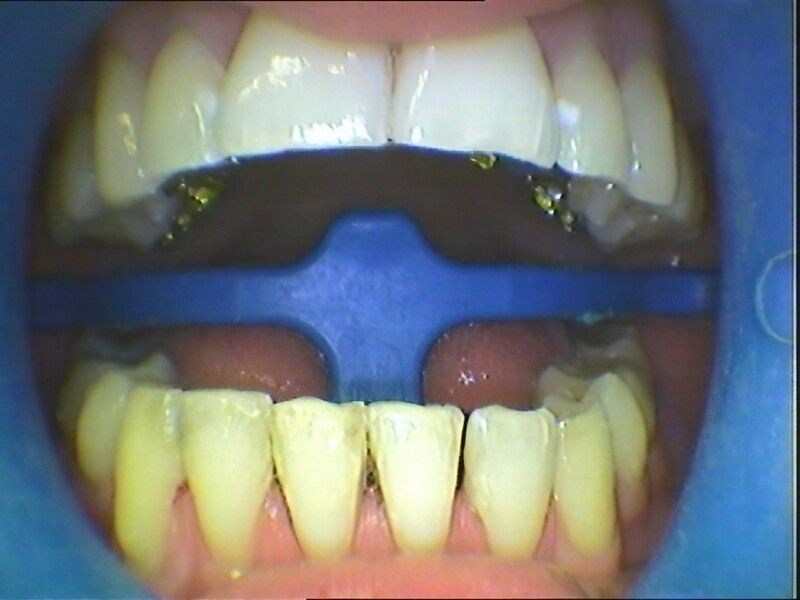

Die Multiband-Klammern werden mithilfe von sogenannten Brackets an den Zähnen befestigt, welche es einmal in einer metallenen und in einer zahnfarbenen Ausführung gibt. Die zahnfarbenen Brackets fallen kaum auf und gelten unter ästhetischen Aspekten als sehr schöne Alternative zur sichtbaren Multiband-Apparatur – einer Zahnspange aus Metall. Unsichtbar wird die kieferorthopädische Behandlung, wenn der Patient mit der Lingual-Bracket-Technik behandelt wird. Hierbei befestigt der kieferorthopädisch tätige Zahnarzt die Elemente auf der Zahninnenseite, sodass von vorne nichts davon zu sehen ist. Diese Behandlungsalternative ist jedoch insgesamt viel aufwändiger. Auch das Six Month Smiles Verfahren bietet Dr. S. Thomas als zertifizierter Absolvent an. Hier steht der Patient als Mensch noch mehr im Mittelpunkt. Das beweist auch die kurze Behandlungszeit von häufig nur sechs bis neun Monaten, von der vor allem Erwachsene gerne profitieren.